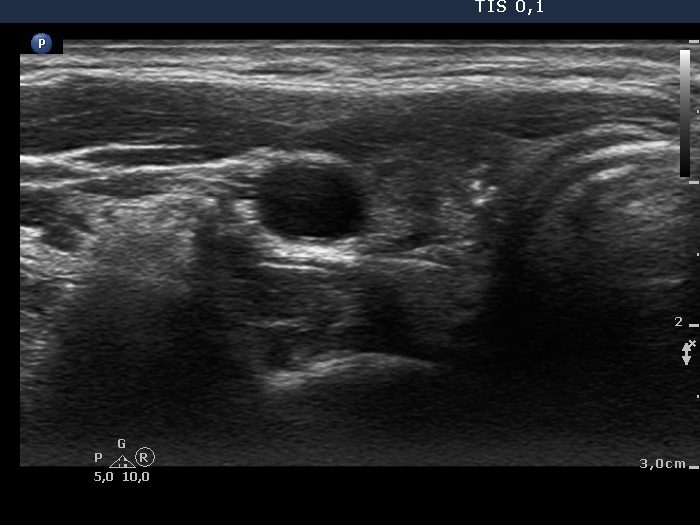

Teamwork - case 894 (ultrasonographic picture 5)

Right lobe, another transverse scan, enlarged view. There are single microcalcifications and a cluster of punctate echogenic foci in the medial part of the nodule.